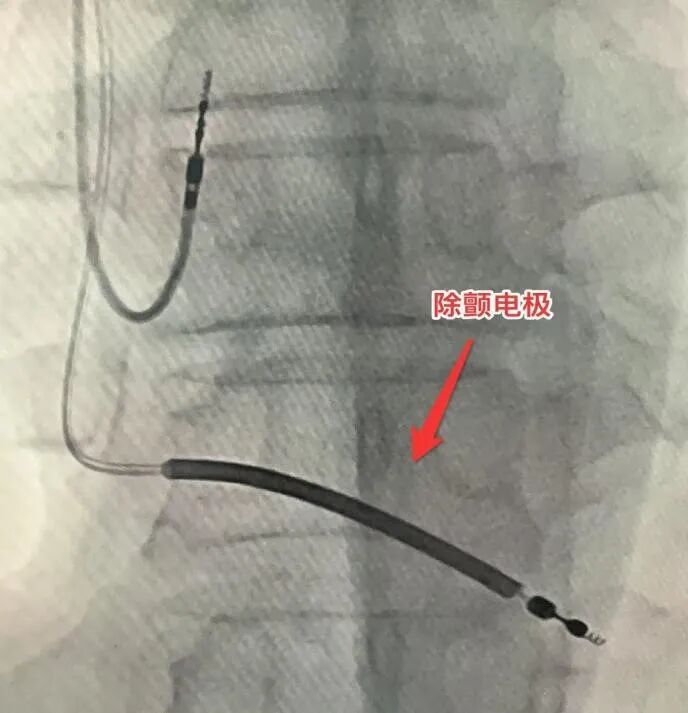

室速室颤与两次电除颤

9月10日凌晨3时19分,CCU监护仪骤然发出警报——康先生突发室速、室颤,心跳骤停并伴随意识丧失。医护人员立即实施电除颤,电流一次次冲击心脏,一次、两次……经过两次全力抢救,康先生终于转危为安。“那之后一度不敢入睡,总担心睡过去就再也醒不来。”这次与死亡擦肩而过的经历,让他真切体会到心梗的凶险。在医护人员细致的病情解释与心理疏导下,康先生紧绷的情绪才逐渐平复。

术后,康先生的心衰症状已得到控制,未再发作,但心电监护仍频繁捕捉到室性心动过速——这是心脏骤停的明确前兆。尽管持续使用抗心律失常药物,情况仍未改善。

此时,植入ICD(植入型心律转复除颤器)成为预防猝死的关键选择,却面临两难境地:一方面,患者因支架植入需长期服用抗血栓药物,此时进行ICD植入手术,将显著增加伤口出血、血肿感染甚至心内膜炎的风险;另一方面,若不植入ICD,患者将持续暴露在随时可能猝死的高风险中。

面对这一临床困境,心内科团队经过全面评估,最终决定迎难而上。在马江伟主任的亲自操作下,手术团队在术中实施精细的止血处理,成功完成ICD植入。术后一周,康先生恢复平稳,未再出现心衰症状,日常活动无不适,真正转危为安,顺利出院。